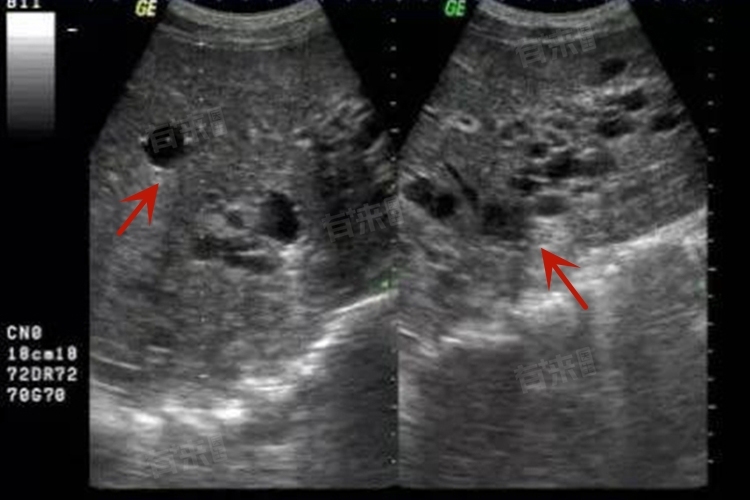

2、影像学检查-超声波:腹部超声是评估肝脏状况的首选方法,可以观察到肝脏大小、形态、质地的变化以及是否存在脂肪肝、肝硬化等情况。